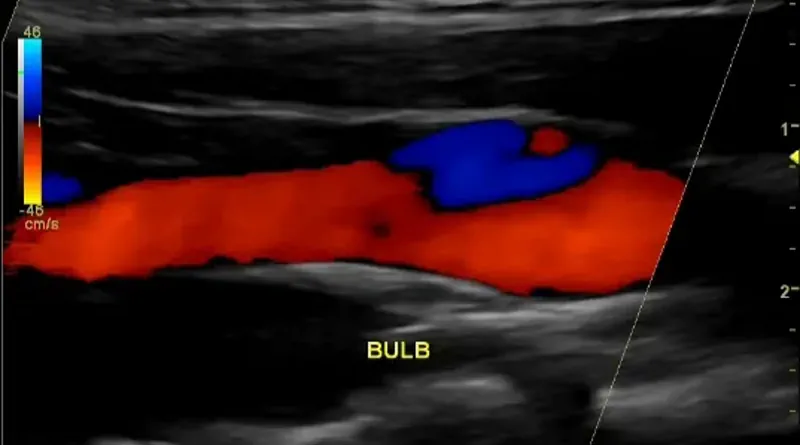

You cannot diagnose a clot in a neck artery without imaging. Imaging means taking pictures of the artery to see if there is a clot. The easiest test is an ultrasound. A carotid artery ultrasound will be able to show blockages in the neck arteries.

Sometimes ultrasound can even show a dissection, but it is not the best test for this purpose. If you need more accurate pictures, you will choose a CT scan or an MRI. In most places it is easier to get a high quality CT scan. A CT scan of the neck arteries will show blockages and any other problems that might exist there. It is very accurate.